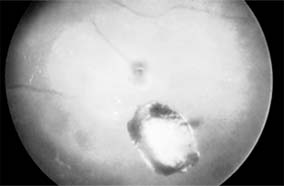

Figure 19-4

Figure 19-4: Choroidal ruptures. (Photo by Diane Beeston.)